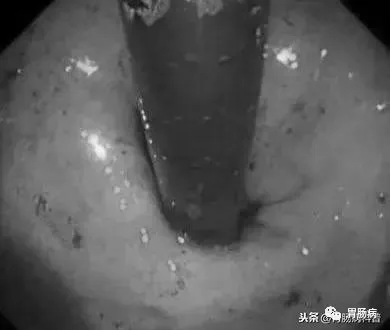

我們再次返回食道內(nèi),發(fā)現(xiàn)持續(xù)有少量鮮血附著于管壁上,邊退鏡邊沖洗,在食道入口處發(fā)現(xiàn)血液量增多,但因食管上括約肌及環(huán)咽肌收縮,入口處黏膜觀察不清,后在胃鏡前端使用透明帽后,視野改善很多。

如下圖:

在食道入口,距門齒約18至20cm處可見片狀黏膜剝脫及條索狀裂傷,持續(xù)滲血。